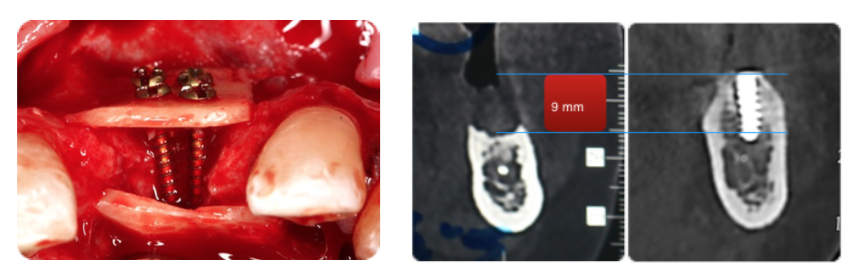

At this point, we need to talk about the reconstructive model proposed by Prof. Khoury (Olsberg, Germany)

This model is based on imitating nature by using autogenous bone.

A bone block is harvested from the retromolar area and then split into two very thin bone blades. These blades will be used to restore the missing cortical walls.

Autogenous from chips, obtained with a safe-scrapper like this one, and a bone crusher, will be placed in the space created by those two thin bone blades.

The whole procedure is performed, if possible, through the already explained tunnel approach.